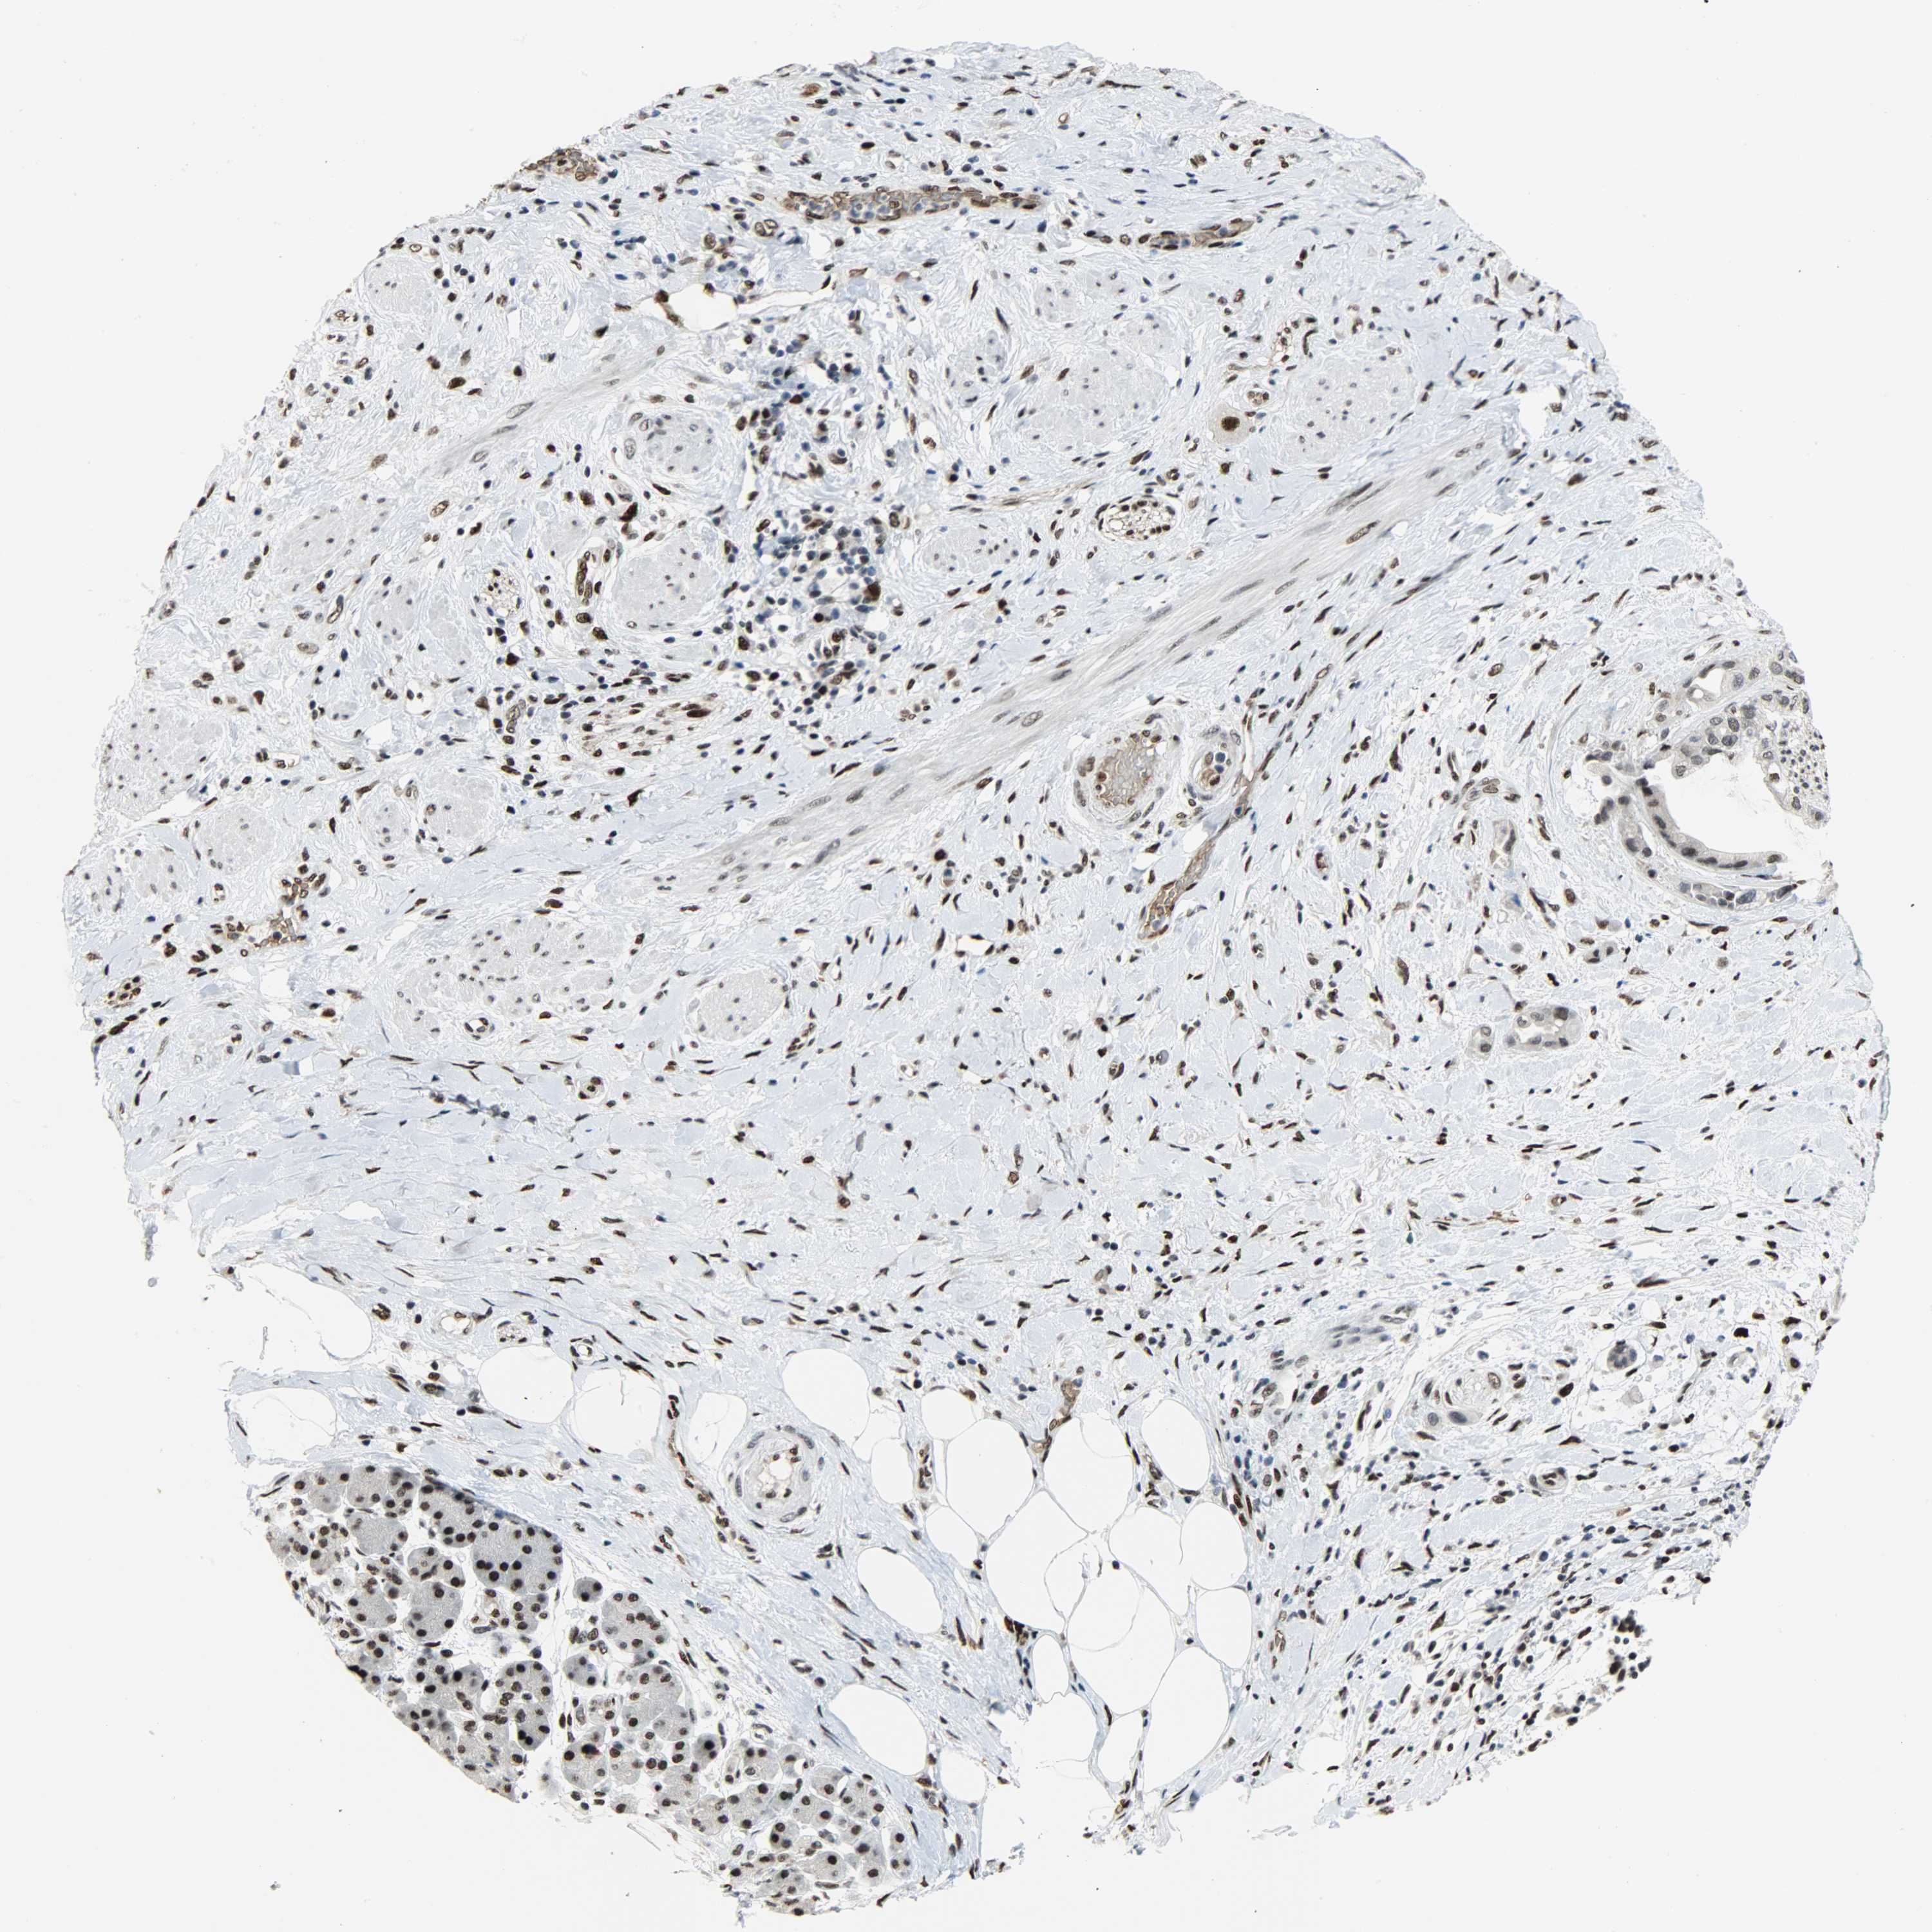

PANCREATIC CANCER - Protein expressioni

A mouse-over function shows sample information and annotation data. Click on an image to view it in a full screen mode. Samples can be filtered based on level of antibody staining by selecting one or several of the following categories: high, medium, low and not detected. The assay and annotation is described here.

Note that samples used for immunohistochemistry by the Human Protein Atlas do not correspond to samples in the TCGA dataset.

Antibody stainingi

Antibody staining in the annotated cell types in the current human tissue is reported as not detected, low, medium, or high, based on conventional immunohistochemistry profiling in selected tissues. This score is based on the combination of the staining intensity and fraction of stained cells.

Each image is clickable and will lead to virtual microscopy that enables deeper exploration of all samples and also displays staining intensity scores, fraction scores and subcellular localization as well as patient and tissue information for each sample.

Antibody HPA069985

Antibody CAB005883

Antibody CAB078687

Antibody CAB080398

Staining

High

Medium

Low

Not detected

Intensity

Strong

Moderate

Weak

Negative

Quantity

>75%

75%-25%

<25%

None

Location

Nuclear

Cytoplasmic/membranous

Cytoplasmic/membranous,nuclear

Adenocarcinoma, NOS

Adenocarcinoma, metastatic, NOS